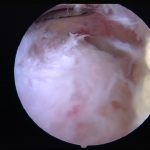

- [VOOR] Eerste peroperatief beeld van ontstoken bursa bij opstarten van endoscopische nettoyage achillespees

- [NA] Beeld na wegname slijmbeurs en bot thv achillespeesinsertie

peroperatieve videobeelden van de verschillende fasen bij een endoscopische achillespeesnettoyage